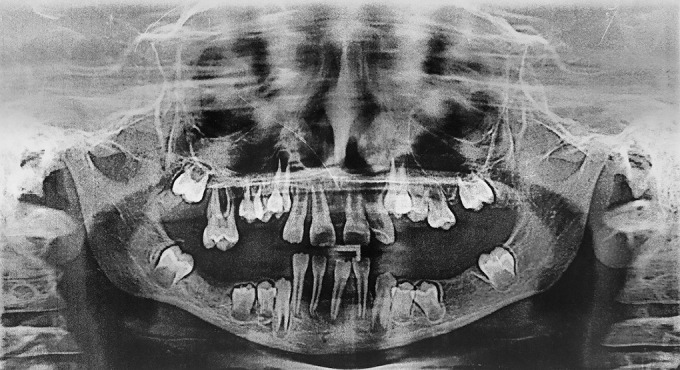

Papillon-Lefèvre syndrome (PLS), also known as keratosis palmoplantaris with periodontopathia and "hyperkeratosis palmoplantaris with periodontosis," is a rare autosomal recessive disorder, characterized by diffuse palmoplantar keratoderma and precocious aggressive periodontitis, leading to premature loss of deciduous and permanent dentition at a very young age. The aim of this article is to revisit PLS, address its diagnosis update and dental management, and to provide insight into the fascinating role of consanguinity in the etiology of this unusual illness. We report the case of two Moroccan sisters aged 5 and 8 years old with PLS who consulted the pedodontics department at the CCTD in Rabat, Morocco, for the early loss of teeth.